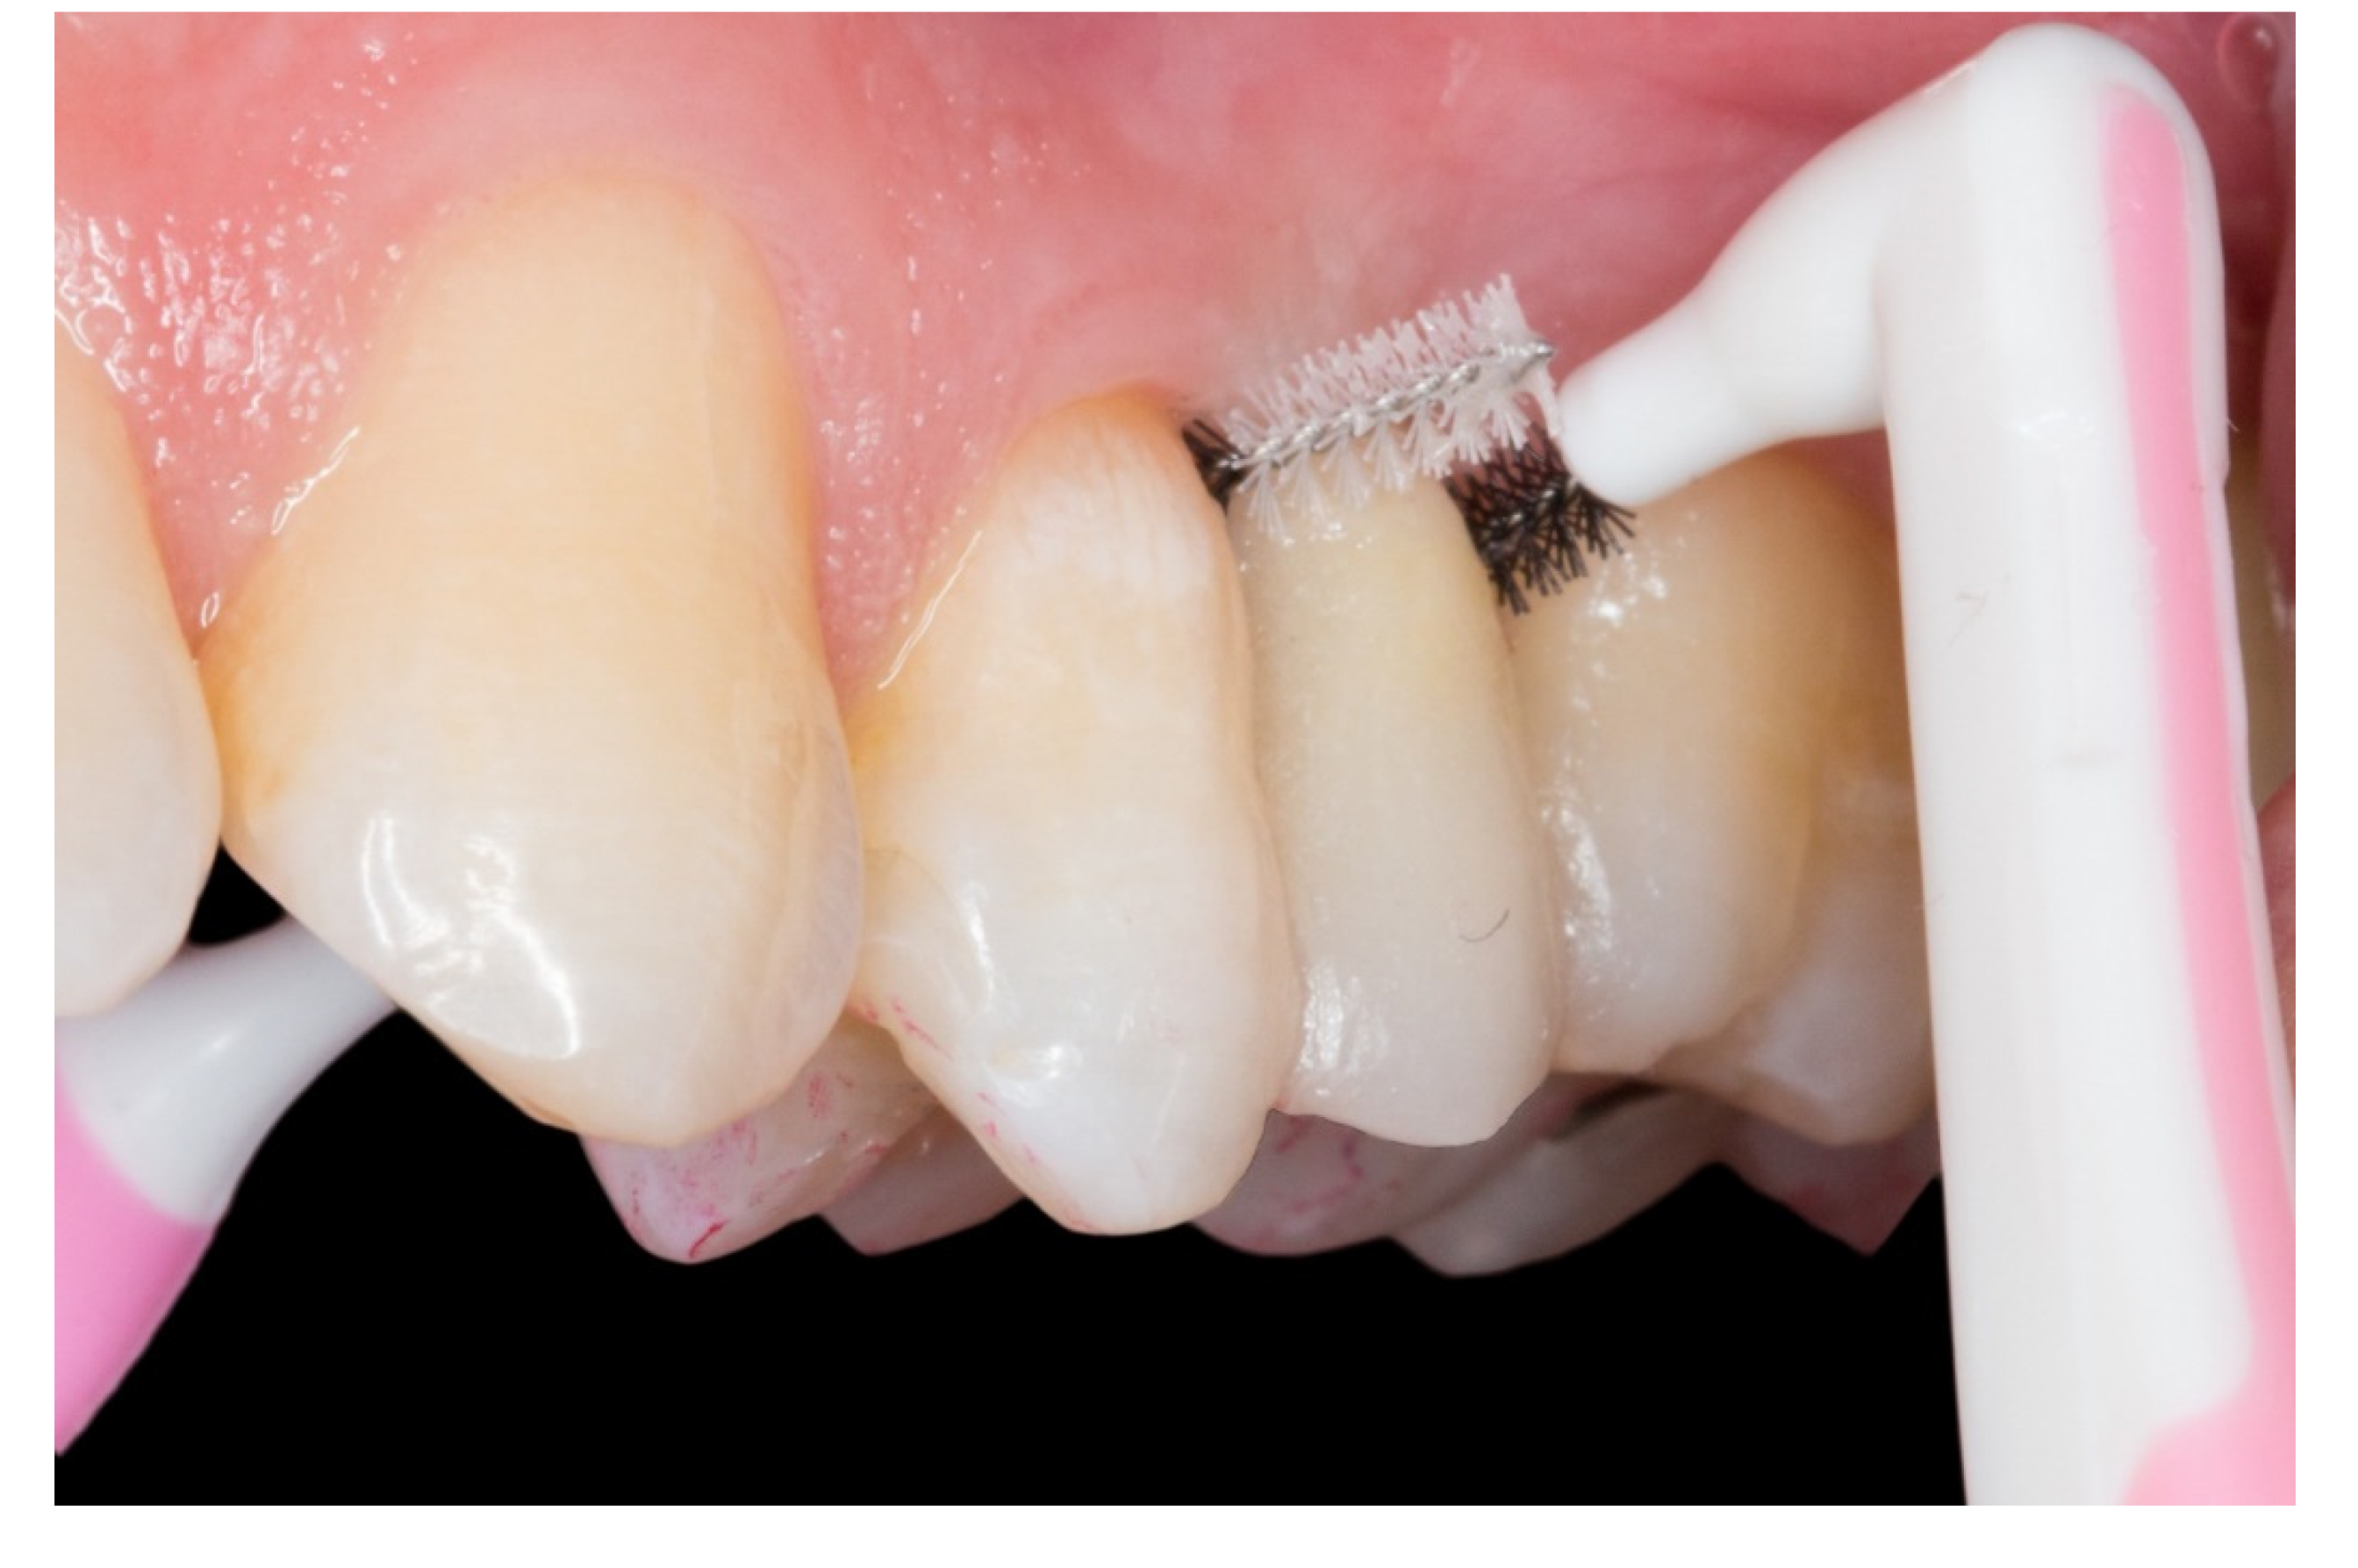

Figure 8.

The embrasures are released allowing adequate interproximal brushing, avoiding periodontal disease and interproximal caries.

On this “T” technique the embrasures are released allowing an adequate interproximal brushing, avoiding periodontal disease and interproximal caries (Figure 8).

All the cases had a clinically acceptable periodontal condition due to the embrasures and were released allowing adequate interproximal brushing. The patients reported no caries, no temperature or pressure sensitivity during the follow-up and all the abutment teeth were vital at the final examination appointments.

Regarding the periodontal aspect and the development of interproximal caries, few articles have been written on this very important aspect [2]. We consider it to be one of the main problems in this type of restoration, due to the need to build a strong and solid framework. Practitioners invade periodontal tissue, generating plaque accumulation causing chronic periodontal inflammation and the development of interproximal caries in the abutment teeth. This technique that we propose uses inlay retainers and two fiberglass pins which form the “T” structure is very solid and stable, allowing the release of embrasures and enabling adequate interproximal brushing. For this reason, as mentioned in the article by Izgi et al. [2], it is important to have follow-ups every six months in order to control the absence of complications in the FRCB and to check up on the abutment teeth. In our opinion, adequate brushing techniques, flossing properly and interproximal brushing should be taught by the practitioners to avoid complications in abutment teeth (interproximal caries and periodontal inflammation).